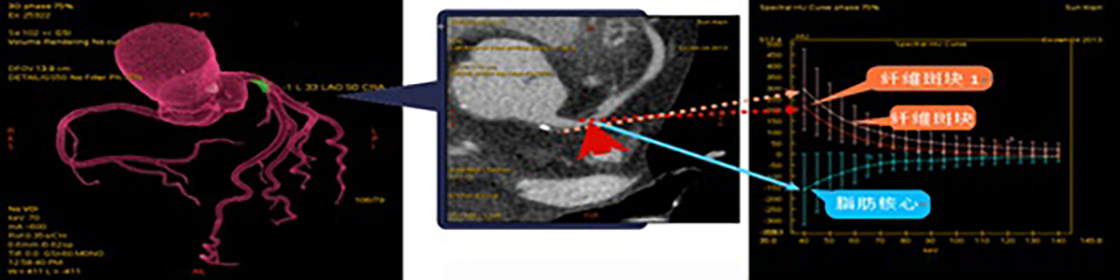

由于軟斑塊的危害程度在一定程度上高于鈣化斑塊,如CT檢查能增加了解軟斑塊的性質(zhì),對于斑塊的穩(wěn)定性判斷及治療將有極大幫助。另外動態(tài)觀察軟斑塊性質(zhì)變化可為病變愈后趨勢判斷提供一定的依據(jù)。實現(xiàn)此功能要求CT檢查在傳統(tǒng)的形態(tài)學成像基礎(chǔ)上增加組織或病變成份判斷的功能。因此對臨床醫(yī)學更有助益的應(yīng)為心臟冠脈能譜成像,應(yīng)用能譜掃描技術(shù)可以對冠脈斑塊成份性質(zhì)進行分析(圖4),預判斑塊的危險性或斑塊演變進程,為進一步治療提供信息。文獻介紹及目前國內(nèi)一些醫(yī)院實際使用效果顯示能譜CT技術(shù)的發(fā)展已可以在自然心率下(無需控制心率)對心臟及冠脈進行常規(guī)成像和能譜成像,成為臨床應(yīng)用覆蓋最廣的超高端CT。